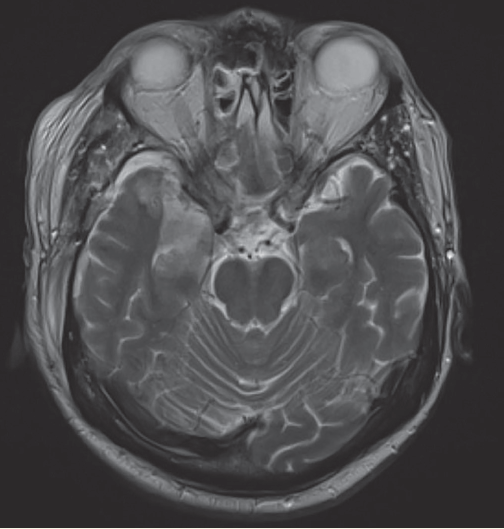

Nicholas V. Mendez, BS; Ayman M. Salah, PhD; Kelsey A. Musgrove, BS; Syed A.A. Rizvi, PhD, MBA; Sultan S. Ahmed, MD; Jasmin Ahmed, BS, MS, MD

​A 33-year-old woman with no significant past medical history presented to our family medicine practice with concern for a headache when she laughs or leans her head forward.